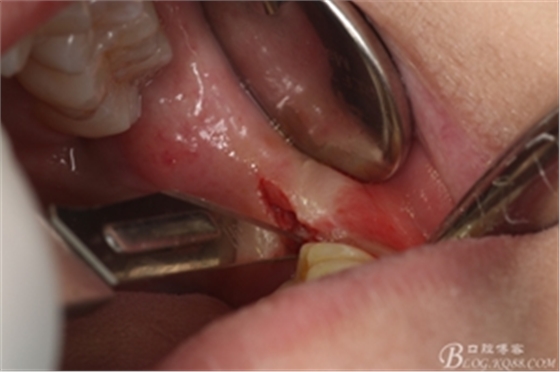

圖6.麻醉效果確定后,在37的近中做垂直松弛切口+遠(yuǎn)中水平切口

圖7. 遠(yuǎn)中的水平切口

圖8. 翻瓣:建議翻小瓣